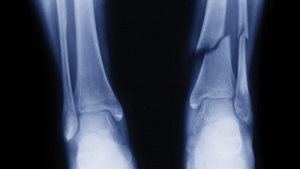

Healing Timelines for Sprains, Fractures and Broken Bones